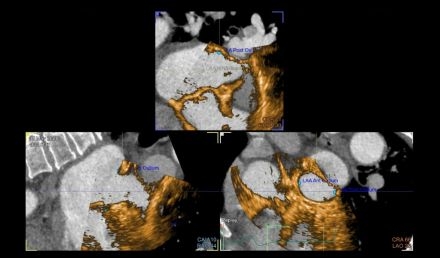

How to Watch a Watchman: Fused Cardiac Imaging for Left Atrial Appendage Closure

Atrial fibrillation (AF) is the most common sustained arrhythmia and is associated with an increased risk for thromboembolic stroke. Anatomically, the left atrial appendage (LAA) is recognized as the most common source of thrombus formation in patients with AF. Life-long anticoagulation is often needed to mitigate stroke risk. However, this requires strict patient adherence and increases the risk of bleeding. Left atrial appendage occlusion (LAAO) devices have been utilized to mitigate stroke risk while allowing for discontinuation of anticoagulation. Accurate visualization and measurement of the appendage is critical to achieve successful LAAO. Multiple imaging modalities have been studied for device sizing and implantation including intraoperative transesophageal echocardiography (TEE) and preprocedural planning with cardiac computed tomography (CT). CT has been shown to provide more detailed visualization of the LAA compared to TEE. Advancements in cardiac imaging allow for fusion of CT with TEE which may further improve procedural outcomes.

This study evaluated LAAO devices implanted using preoperative CT fused with intraoperative TEE (CT-TEE fusion) compared to those implanted with TEE without fused imaging. Key outcomes included procedure duration, quantity of LAAO devices used intraoperatively, incidence of adverse events, and 45-day leak.